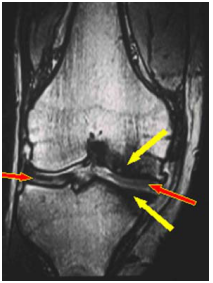

图片

• MRI:可能有助于早期诊断,特别是当关节受累时,表现出一种独特的炎症和强化显像,软骨和软骨骨骺信号异常;同时,MRI水成像对判断内耳病变时也有重要价值。